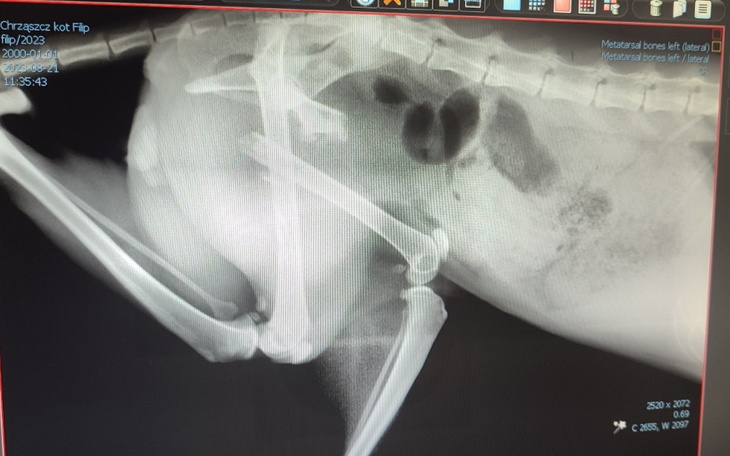

Trafił do nas kot, rudy Filipek. Z poważnym złamaniem kości udowej z przemieszczeniem. Uraz elimuje go z adopcji i nie pozwala żyć na wolności.

Ten stan może zmienić tylko operacja.